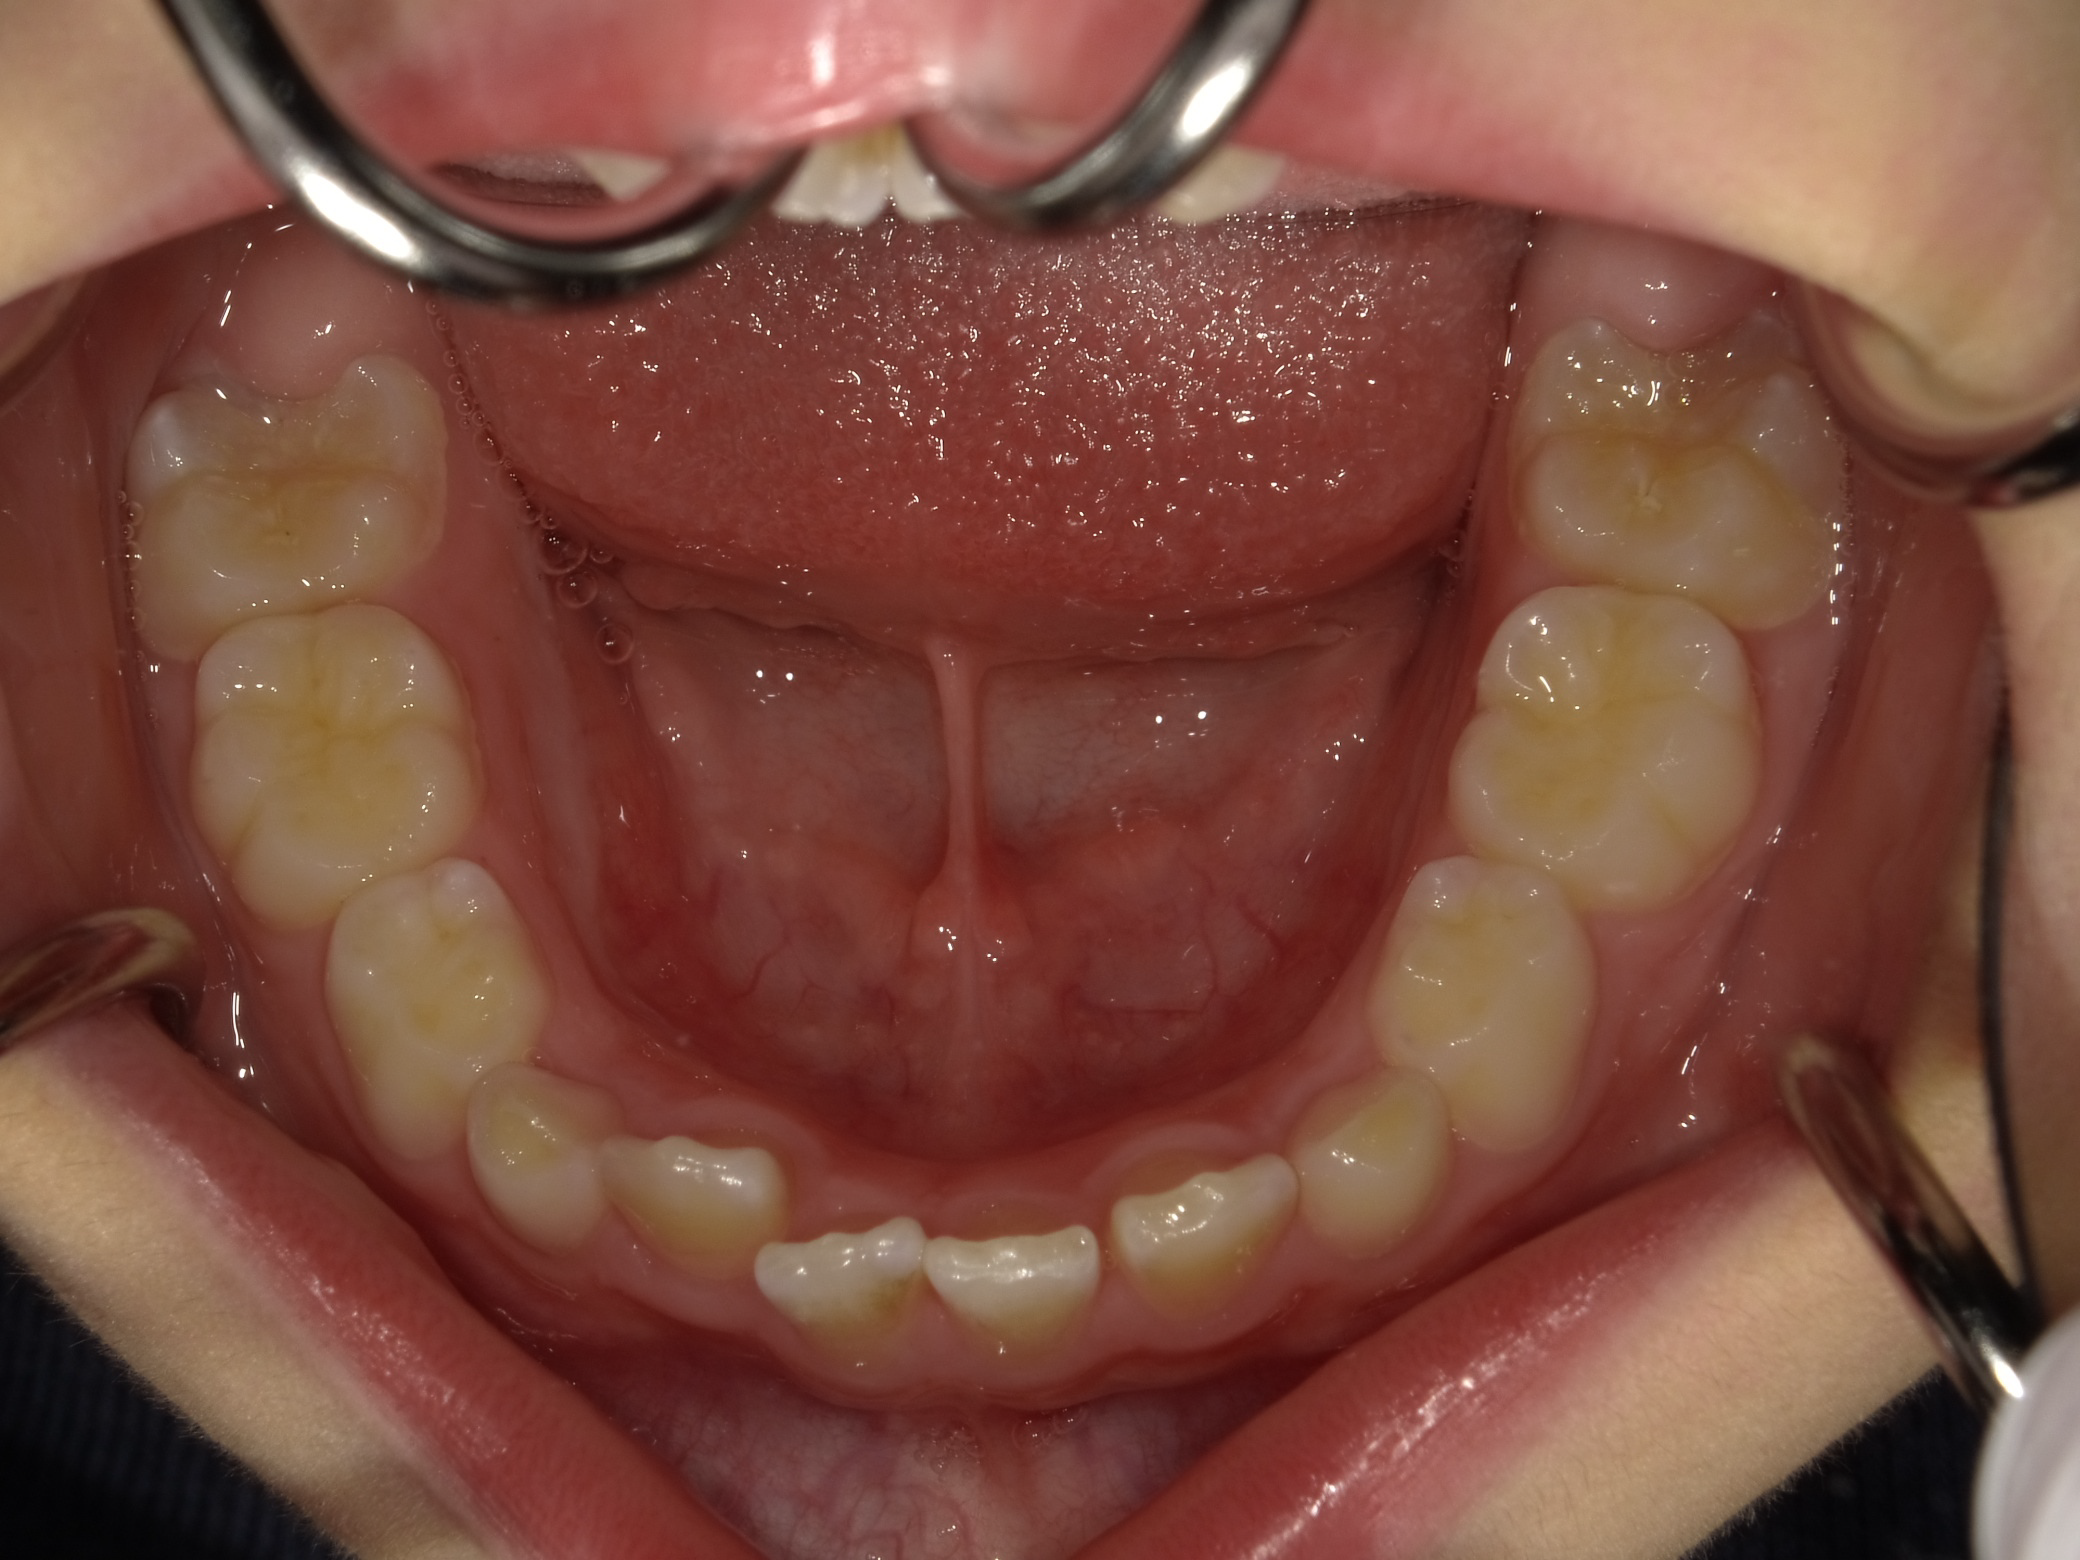

1期矯正の経過

時間はかかりますが、だいぶ凸凹が改善してきました。しかしまだ正面か見ると下の歯が見えません。

今回は上の歯が出過ぎているというより、下の顎は引っ込みすぎていると診断し、下顎を前に誘導する装置を使用します。